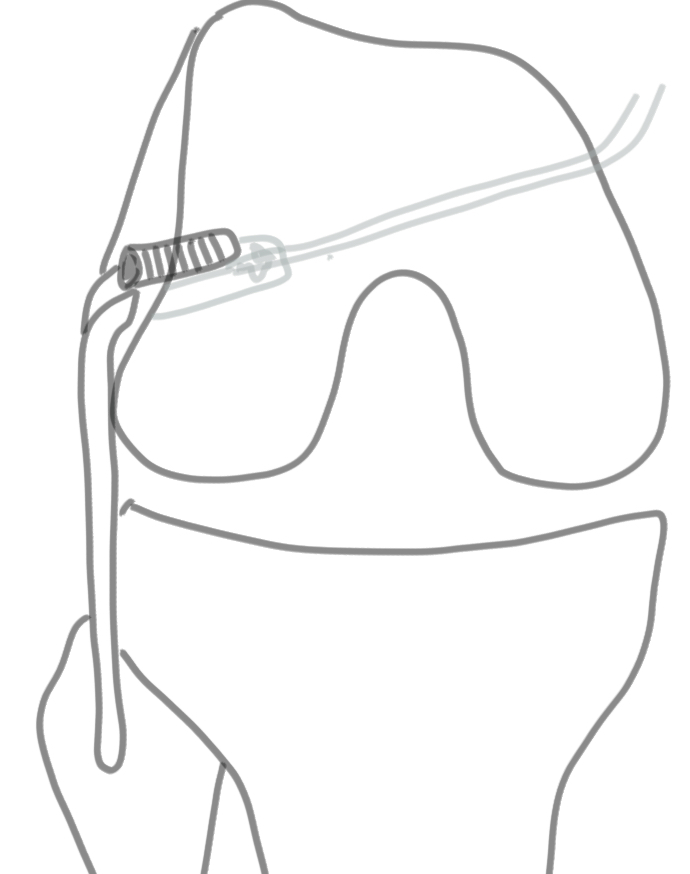

B. Larson Loop

Concept

- single fibular tunnel as per LaPrade

- single LCL tunnel

- two limbs of graft to constitute LCL and popliteofibular

- pull both limbs into femoral tunnel and secure with screw